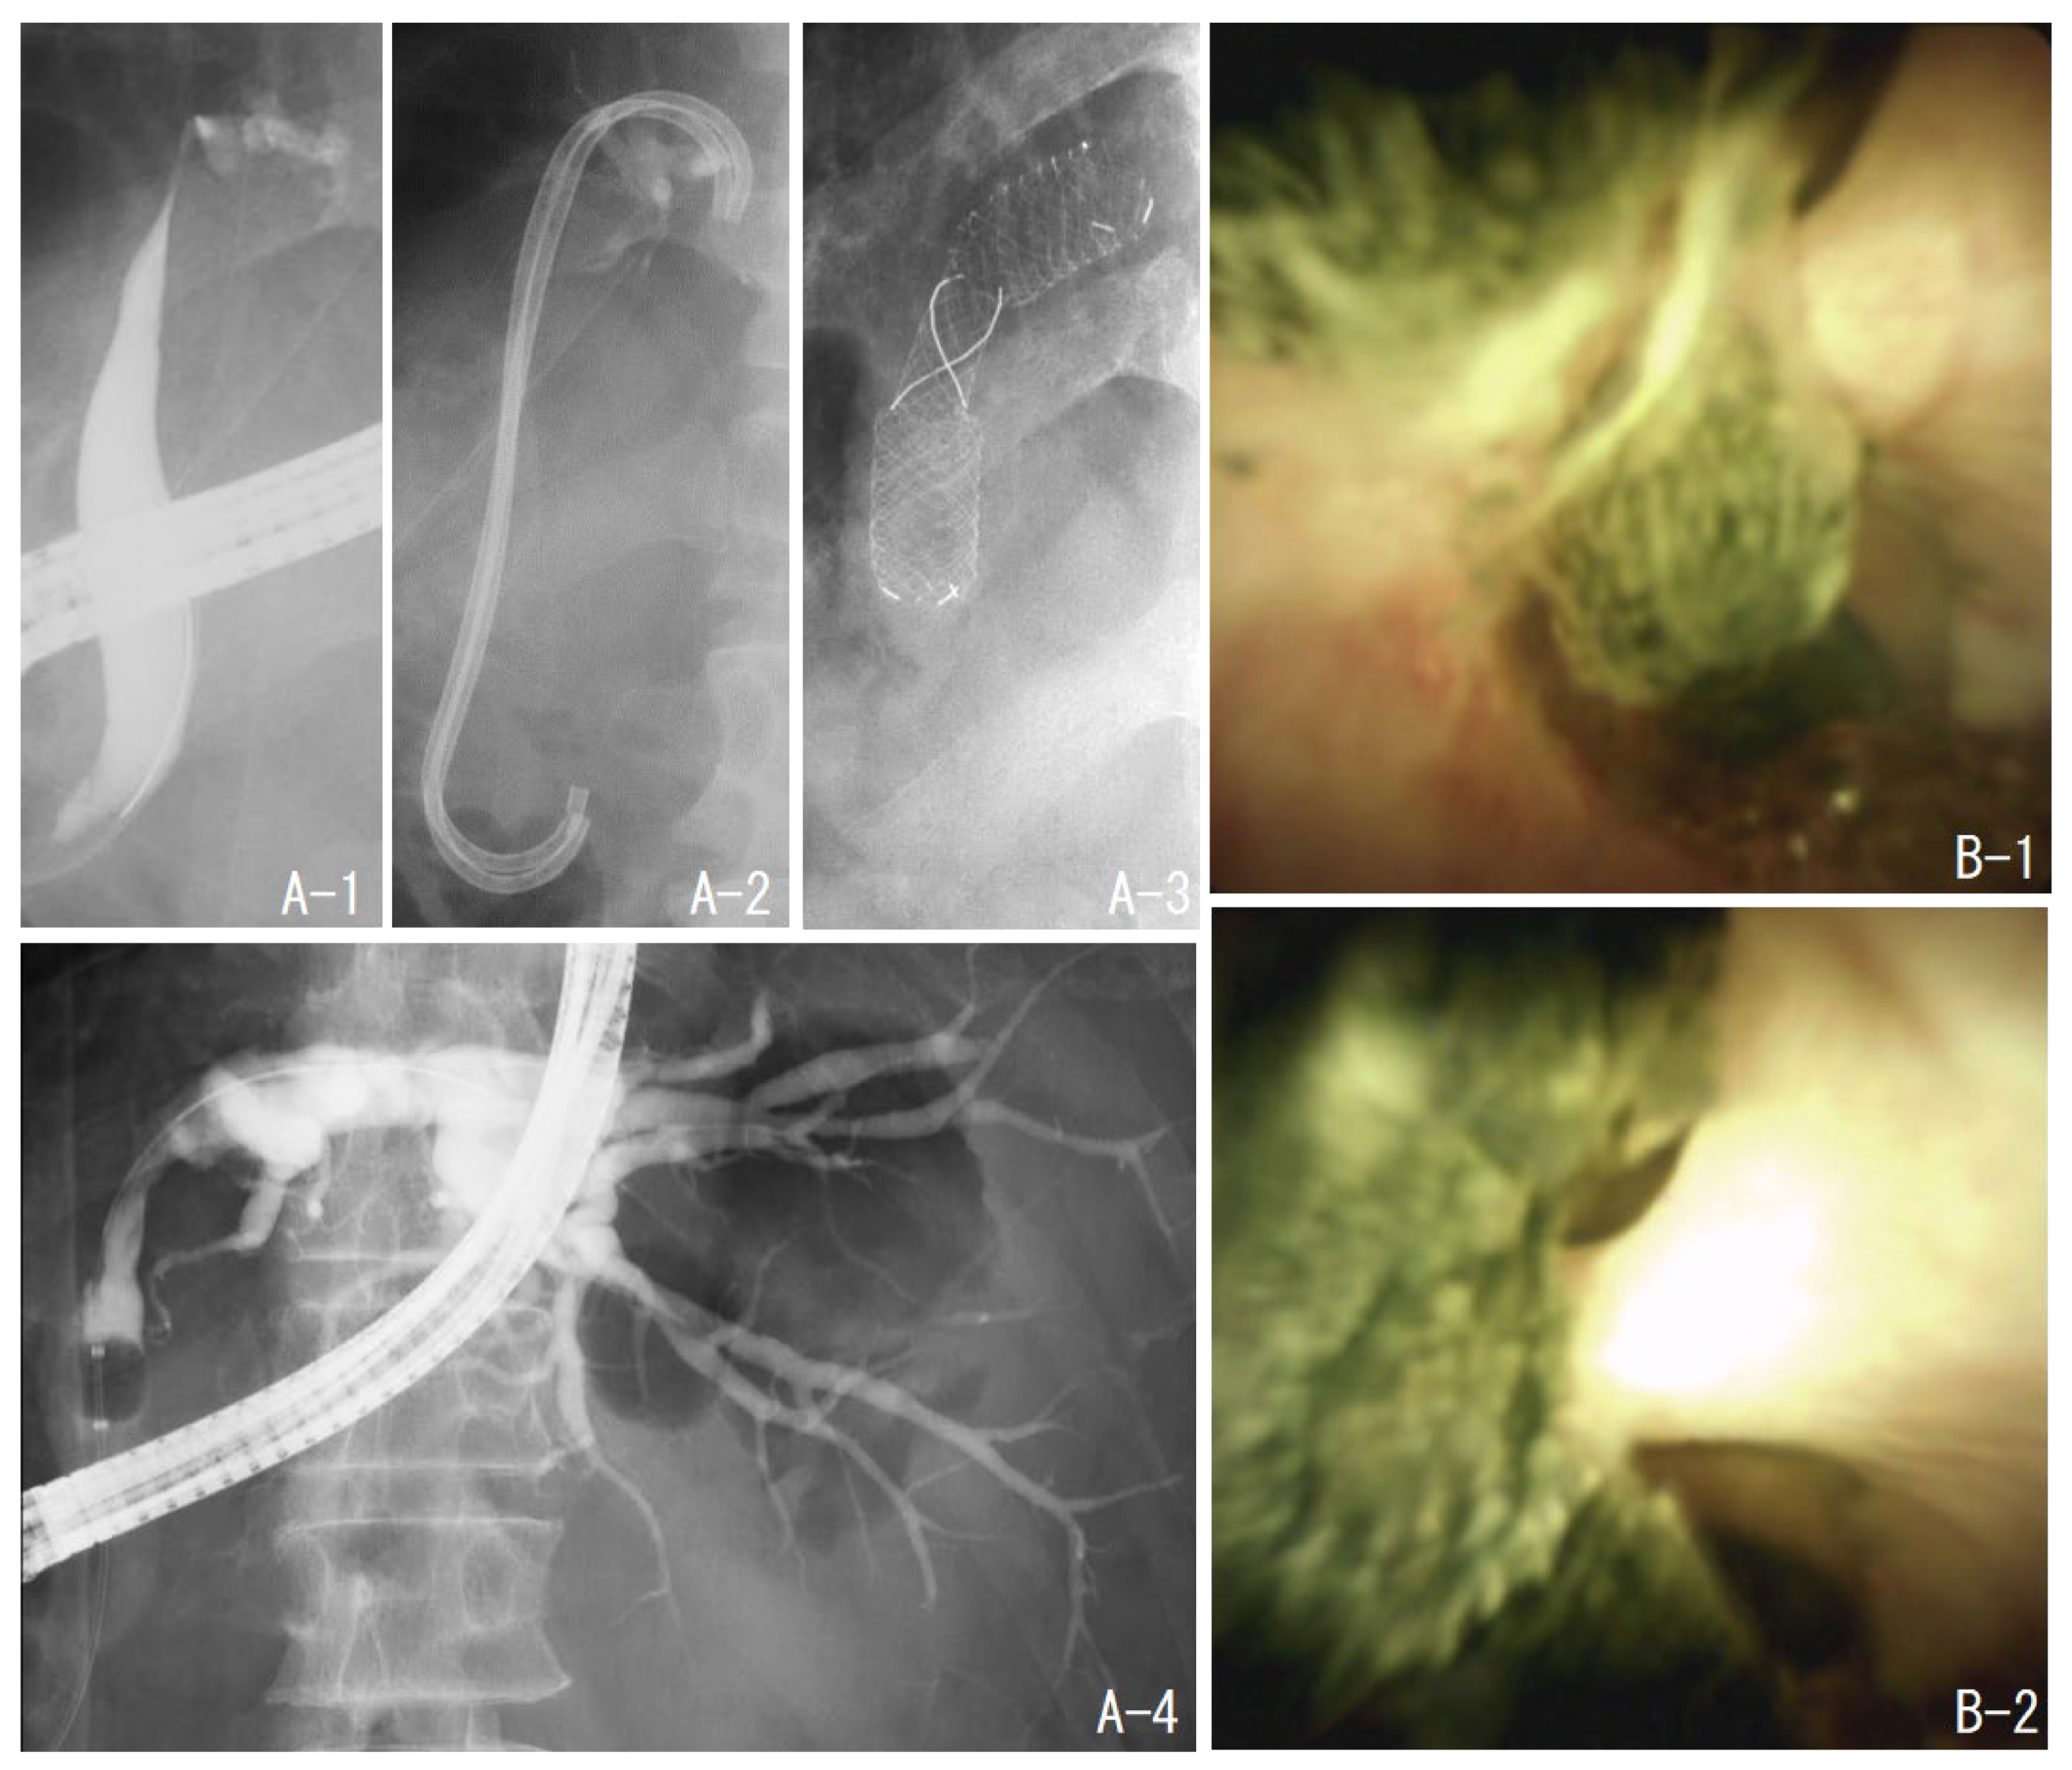

Figure 1.

Case 1. The beginning of the right anterior columnar canal was narrowed (B-1), and stones filled the upstream of the stenosis (A-1). Balloon dilation of the stenosis was performed (A-2). The stone was removed by electrohydraulic shockwave lithotripsy under peroral cholangioscopy (B-2,B-3), and cholangiography was performed to confirm the absence of residual stones (A-3).

The patient had undergone a right hepatectomy for hepatocellular carcinoma. Postoperatively, the left intrahepatic bile duct became stenosed and stones formed upstream of the stenosis. After four sessions of treatment, including EHL under POCS, the stone was almost completely removed. However, the stenosis remained and was difficult to dilate with a plastic stent; hence, a self-expandable metal stent (BONASTENT® M-Intraductal, MEDICO’S HIRATA Inc., Osaka, Japan) was placed. When the stent was removed one month later, the stenosis had expanded (Figure 2).

Figure 2.

Case 2. The patient had a stenosis of the left hepatic duct after the right hepatectomy (A-1). There were multiple stones upstream of the stenosis (B-1,B-2). The stones were removed by electrohydraulic shockwave lithotripsy under oral cholangioscopy. However, the stenosis was not dilated by the plastic stent (A-2); hence, a self-expandable metallic stent was placed (A-3). One month later, the stent was removed, and cholangiography showed improvement of the stenosis (A-4).